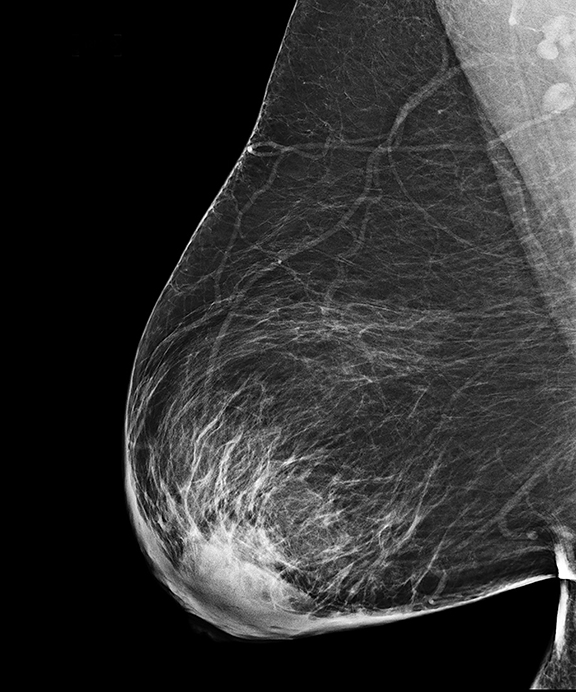

Аномалии молочной железы: медицинские примеры и визуализация

Раздел: Мудрость в деталях